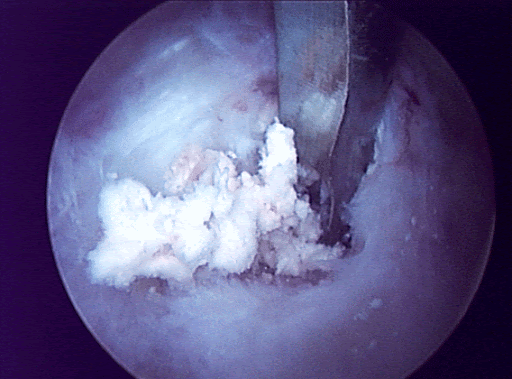

• ultrasound-guided needle lavage vs. needle barbotage : especially in the resorptive stage

• surgical decompression of calcium deposit : for refractary cases. risk of capsulitis